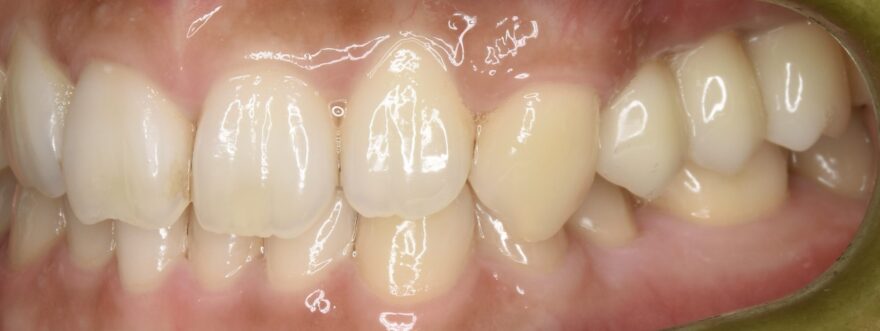

治療後の口腔内写真

症例の治療に必要な標準的な費用

1,012,000円(税込)

奥歯インプラント2本→1本あたり440,000円(税込)

前歯プレミアムセラミックダミー2本→1本あたり132,000円(税込)